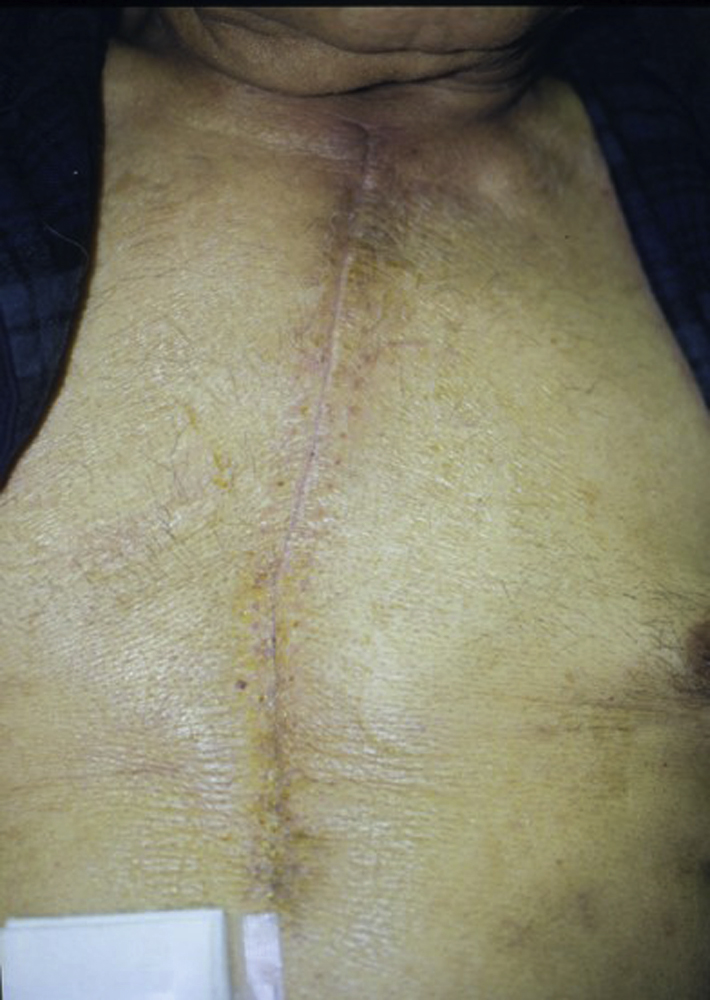

The patient had a slow recovery with a complicated postoperative course. His sternal wound eventually healed well without any major issues related to the sternal wound reconstruction. He was discharged from the hospital 49 days after the open-heart surgery and 26 days after the sternal flap reconstruction. The drain was removed about 3 weeks after the sternal wound closure ( Fig. 21.5 ).

The patient had a well-healed sternal wound after bilateral pectoral major myocutaneous advancement flap reconstructions for sternal wound dehiscence ( Fig. 21.9 ). His postoperative course after total gastrectomy was complicated by prosthetic valve endocarditis, sepsis, and multisystem organ failure. He eventually died 2 months after the total gastrectomy.